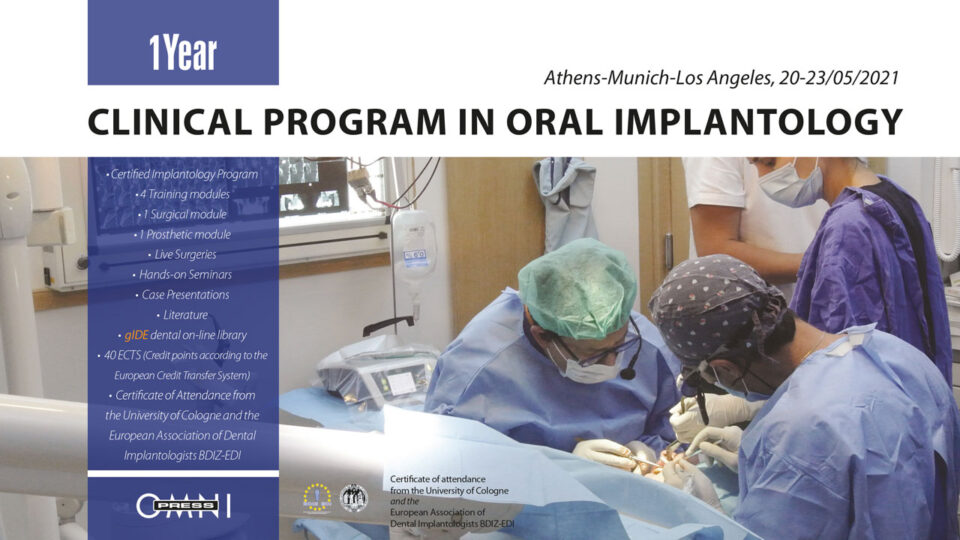

Ημερομηνίες διεξαγωγής: Περίοδος Ι : 24-27 Ιουνίου 2021, Αθήνα, Περίοδος II.15-18 Ιουλίου 2021, Αθήνα, Περίοδος III. 23-25 Ιουλίου 2021, Αθήνα, Περίοδος IV. 30 Σεπτεμβρίου - 03 Οκτωβρίου 2021, Αθήνα, Περίοδος V. Οκτωβρίος 2021, Αθήνα, Περίοδος VII. 5 - 9 Νοεμβρίου 2021, Μόναχο - Γερμανία, Περίοδος VIII. 20-24 Σεπτεμβρίου 2021, Los Angeles & Loma Linda Univercity, USA